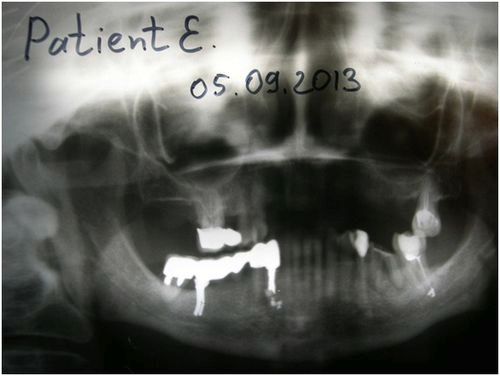

R-фія 43: ГАНГ інтегрований в кістку. Кістковий регенерат має підвищену, у порівнянні з органотіпом, щільність. Кіста ліквідована. Повторна ортопантомограмма виявила чітку тенденцію до заміщення кістозної порожнини здорової кістковою тканиною.

ОПГ 2. Через два місяці від початку лікування порожнину під 44 зменшилася в розмірі, ГАНГ інтегрує з навколишнього порожнину кісткою. 43 запротезірован внутрішньокореневого культевой срібною вкладкою для подальшої фіксації на вкладку металокераміки.

Ортопантомограмма, проведена після протезування, підтвердила позитивний результат проведеного Їжачій Л.В. лікування. Проводиться профілактичне динамічне спостереження.

ОПГ 3. ГАНГ інтегрував в кістку, кістковий регенерат має підвищену щільність. Осередок локального остеопорозу, викликаний зростанням кісти 43 заміщений кісткою. Периодонт 43 збережено.

R-фія 43. Через півроку після початку лікування ГАНГ інтегрував з кісткою, утворивши регенерат кісткової тканини підвищеної щільності. Кіста ліквідована.